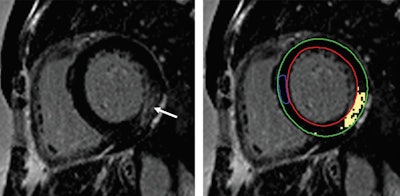

MR images of a 45-year-old woman with Fabry disease who experienced unsustained ventricular tachycardia following cardiac MRI. Basal short-axis late gadolinium-enhanced (LGE) cardiac MRI (left) demonstrates midwall enhancement most prominent at basal inferior lateral wall (arrow). Basal short-axis LGE image demonstrates (right) quantification of LGE (epicardial contour [green], endocardial contour [red], normal reference myocardium contour [blue], and extent of LGE with signal intensity threshold of 4 standard deviations above visually normal myocardium [yellow]). Images courtesy of Radiology."These data support the necessity for future larger studies to evaluate whether cardiac MRI can be used to prospectively identify high-risk patients and to establish Fabry disease-specific prediction models," the authors concluded.